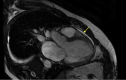

McLeod's syndrome (MLS) is an X-linked disorder caused by mutations in the XK gene with neurological manifestations as well as cardiomyopathy. This is a case of acute exacerbation of heart failure in a 44-year-old White male with a confirmed diagnosis of MLS, which was managed with guideline-directed medical therapy and placement of an implantable cardioverter defibrillator with recovery in ejection fraction.

Keywords: McLeod’s syndrome; guideline-directed medical therapy; implantable cardioverter defibrillator; late galodinium enhancement.